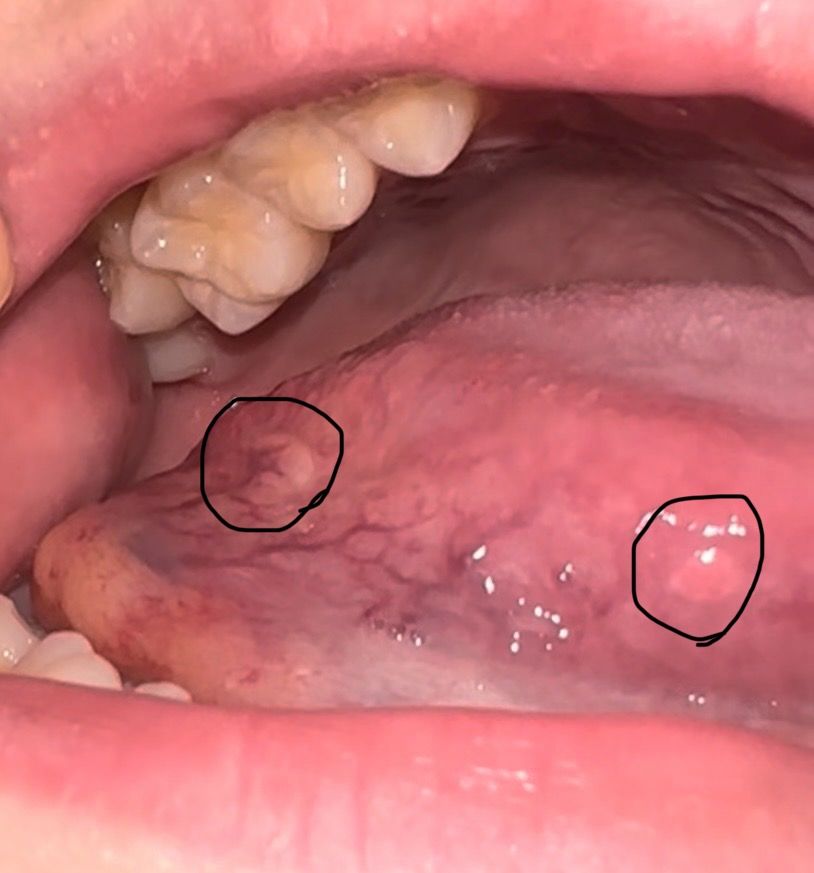

혀에 돌기랑 하얀색 병변이 보여요 병원 가봐야할까요?

외쪽 동그라미 보시면 좀 하얀색 미끈미끈하고 부드러운 부분이 보이고 막 튀어나오진 않았어요. 오른쪽은 핑크색 혹같은게 있는데 쪼금 튀어나온 것 같아요. 이거 병원가보는게 좋을까요?